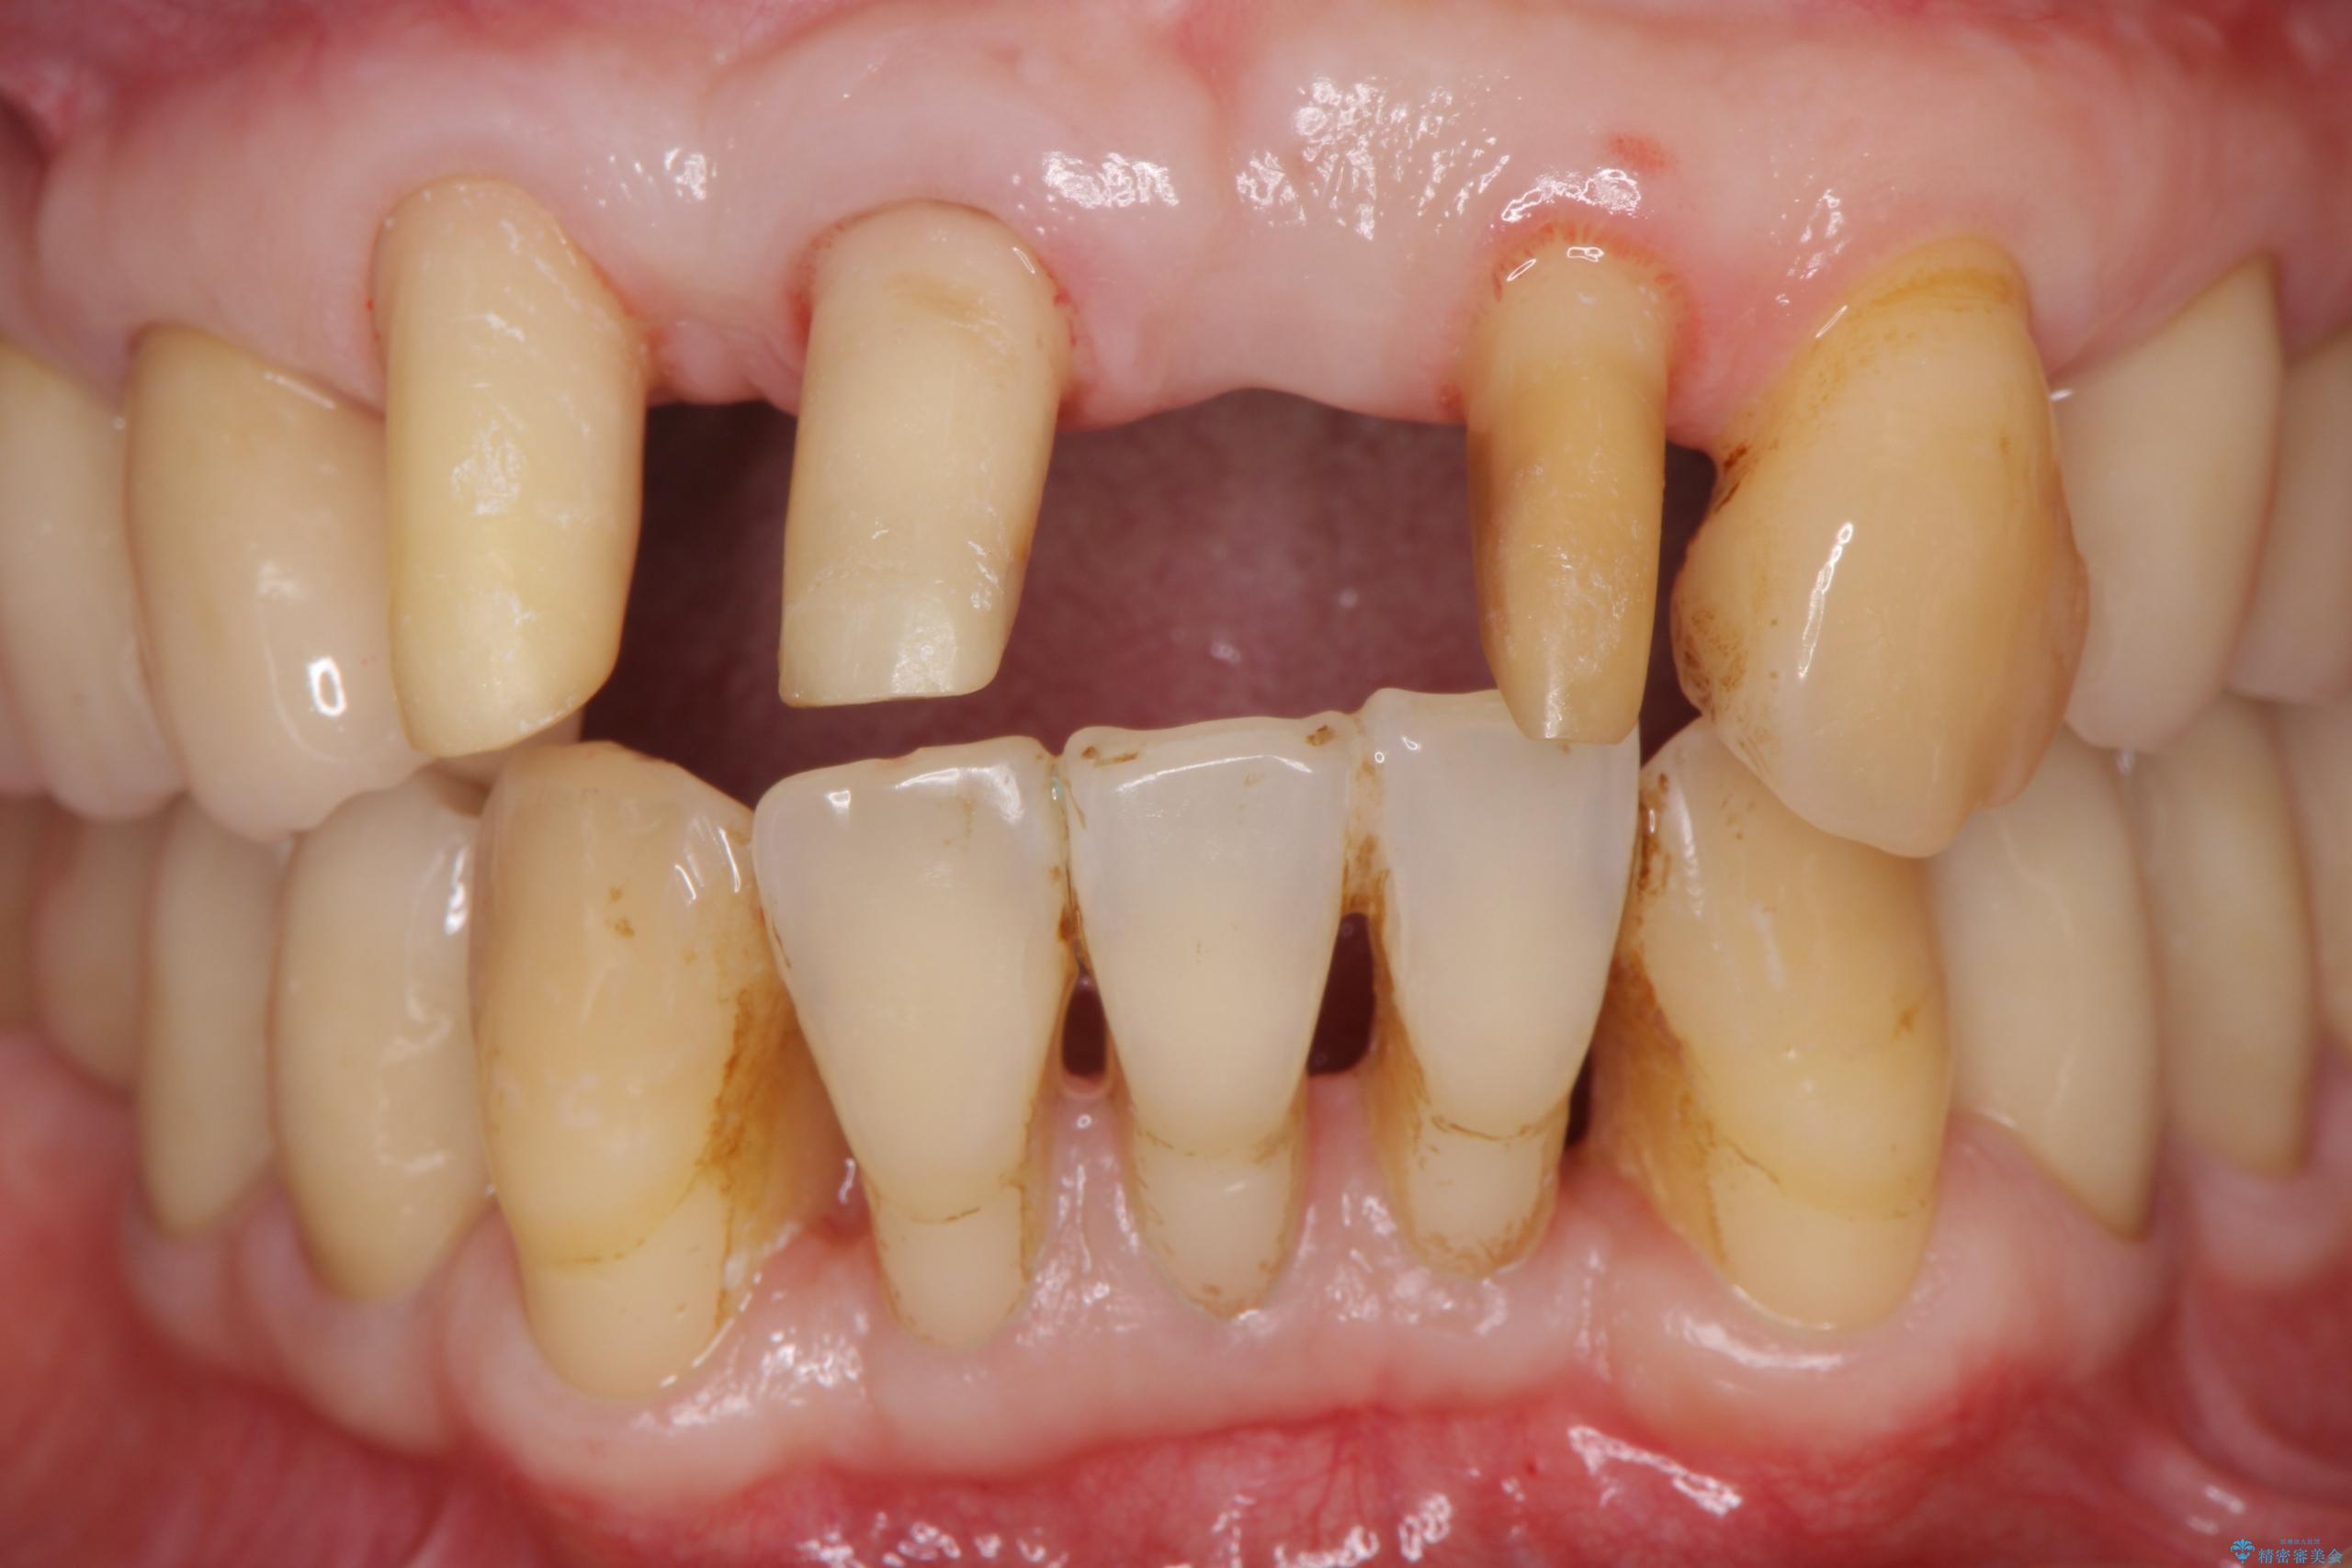

治療中

歯の総合的なマネージメントを行う包括的歯科治療の実践[ 歯周病・矯正・セラミック補綴 ] 治療中画像 歯の総合的なマネージメントを行う包括的歯科治療の実践[ 歯周病・矯正・セラミック補綴 ] 治療中画像 歯の総合的なマネージメントを行う包括的歯科治療の実践[ 歯周病・矯正・セラミック補綴 ] 治療中画像 歯の総合的なマネージメントを行う包括的歯科治療の実践[ 歯周病・矯正・セラミック補綴 ] 治療中画像 歯の総合的なマネージメントを行う包括的歯科治療の実践[ 歯周病・矯正・セラミック補綴 ] 治療中画像 歯の総合的なマネージメントを行う包括的歯科治療の実践[ 歯周病・矯正・セラミック補綴 ] 治療中画像 歯の総合的なマネージメントを行う包括的歯科治療の実践[ 歯周病・矯正・セラミック補綴 ] 治療中画像 歯の総合的なマネージメントを行う包括的歯科治療の実践[ 歯周病・矯正・セラミック補綴 ] 治療中画像 歯の総合的なマネージメントを行う包括的歯科治療の実践[ 歯周病・矯正・セラミック補綴 ] 治療中画像 歯の総合的なマネージメントを行う包括的歯科治療の実践[ 歯周病・矯正・セラミック補綴 ] 治療中画像 歯の総合的なマネージメントを行う包括的歯科治療の実践[ 歯周病・矯正・セラミック補綴 ] 治療中画像

まず、保存の難しい歯を抜去したのち矯正治療を行い歯並びの改善、歯周ポケットを除去したことで安定した歯周環境、咬合関係を作り出すことができました。